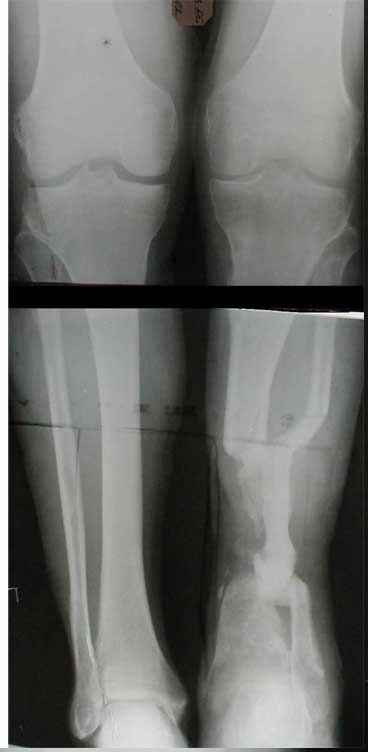

В приложении - моё наблюдение (возможно, уже представлял, тогда

извините).

Нога попала в пресс.

Ко мне больной попал черз 1,5-2 года после травмы и нескольких

операций с синегнойной инфекцией на всю голень. Меня пригласили на консультацию

насчет ампутации.

Лечил я его месяцев 8.

Малоберцовка полностью перестроилась, нога опороспособна.

При ходьбе на дальние расстояния пользуется тростью.

Осталась трофическая язва, периодически закрывается.

Клинические снимки где-то есть, но не очень качественные.

Один из вариантов.